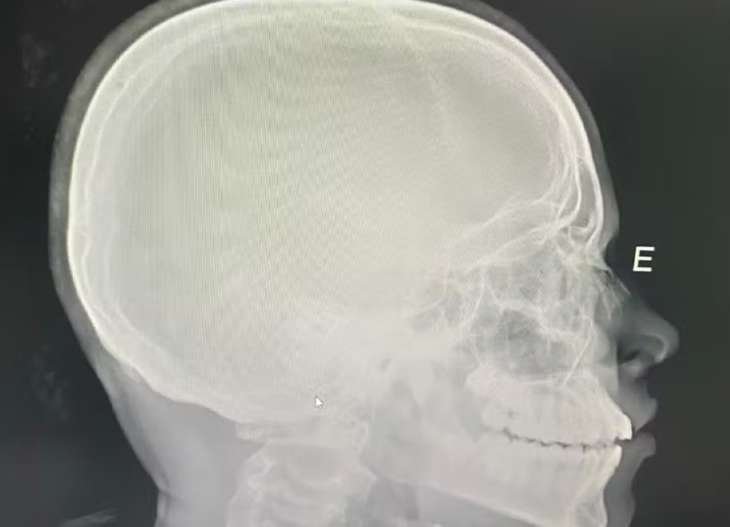

O adolescente passou por cirurgia nesta quarta-feira (11), em Porto Nacional. O caso está sendo investigado pela Polícia Civil. A Secretaria da Segurança Pública informou que o inquérito corre em segredo de justiça por envolver menores de idade.